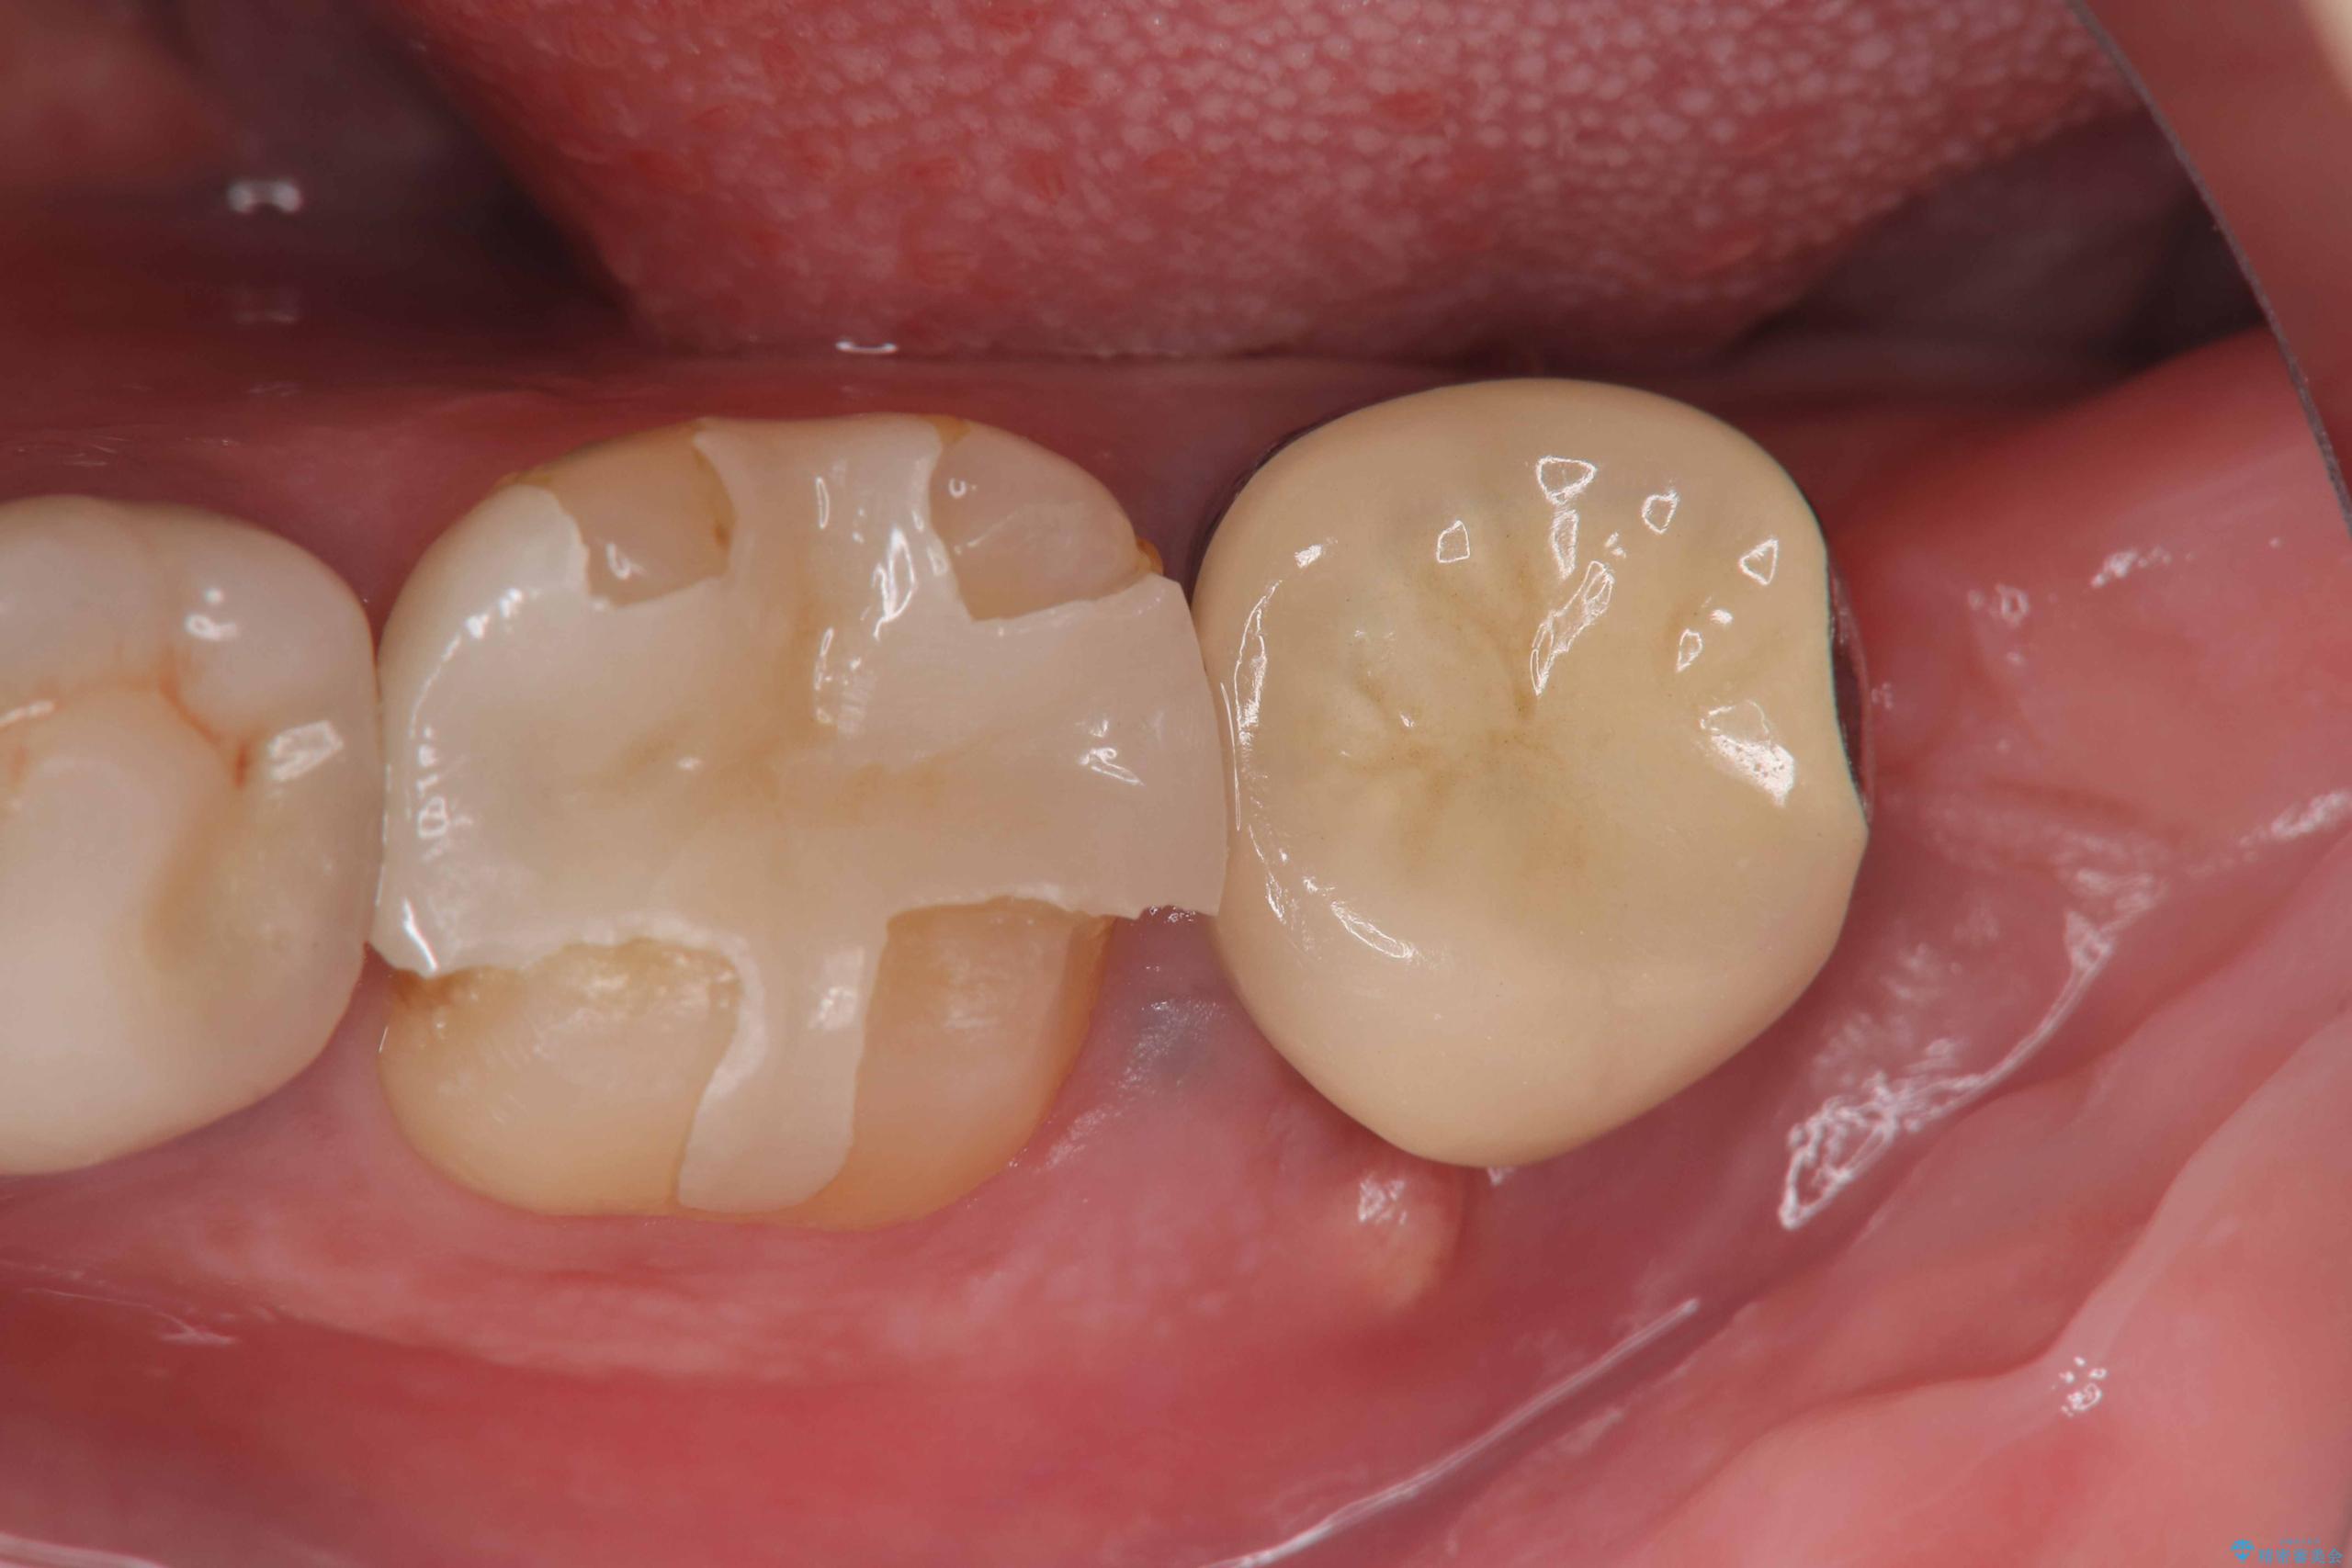

また、左下6番には形態が不自然で適合不良のセラミックインレーが装着されていたため、二次カリエスのリスクを考慮し、オールセラミッククラウンによる治療を行いました。